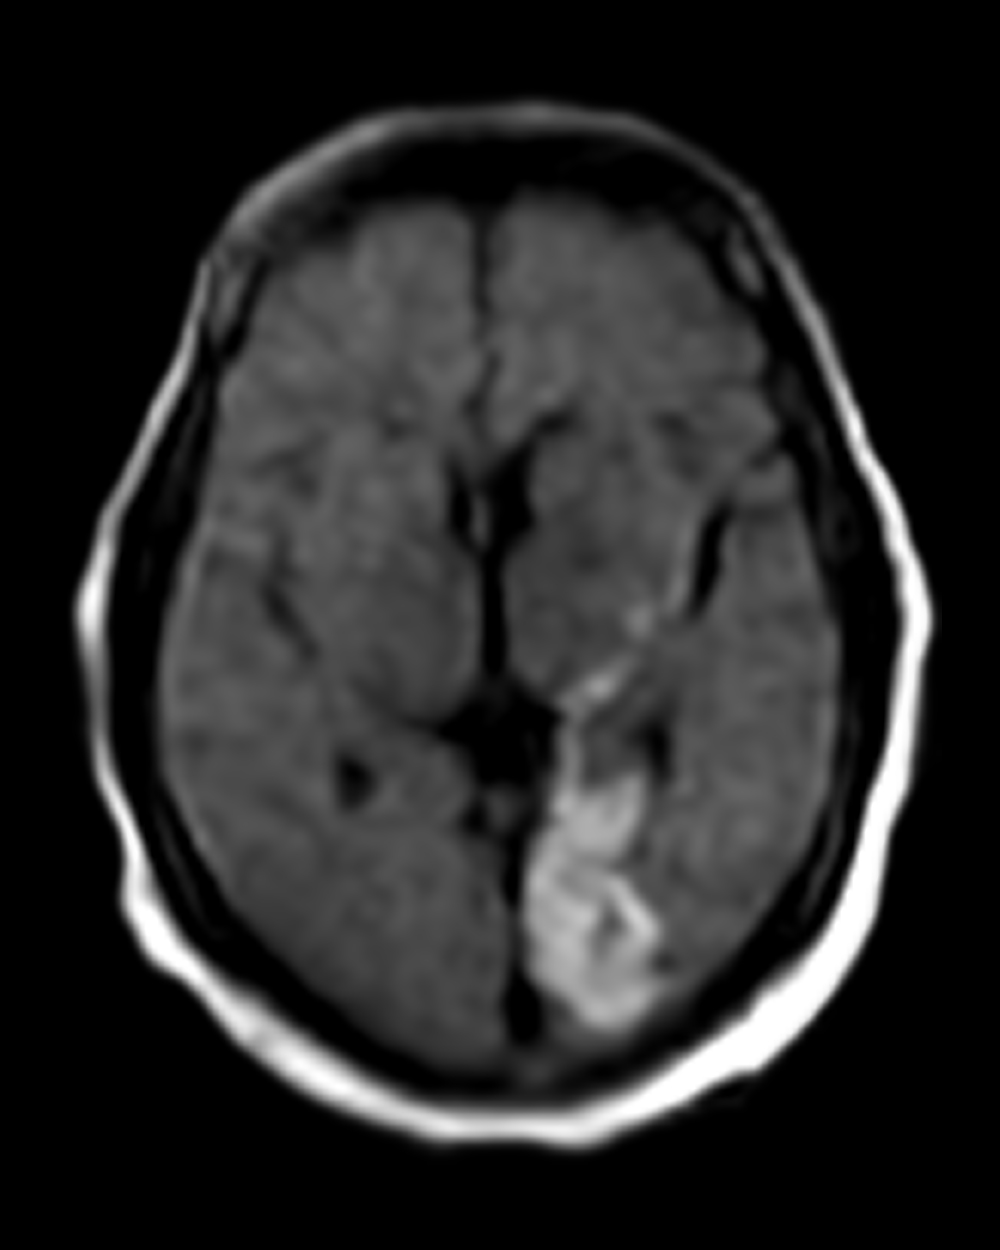

Left Posterior Cerebral Infarct

Patient Profile

72-year-old patient presented to the ED with acute-onset visual disturbance and right-sided weakness.

Portable MRI

The Swoop system was driven to the patient’s bedside and ready to scan within minutes

Stroke Detected

Swoop system images allowed clinicians to confirm infarcts

Triage

Patients were triaged to stroke units for management and monitoring